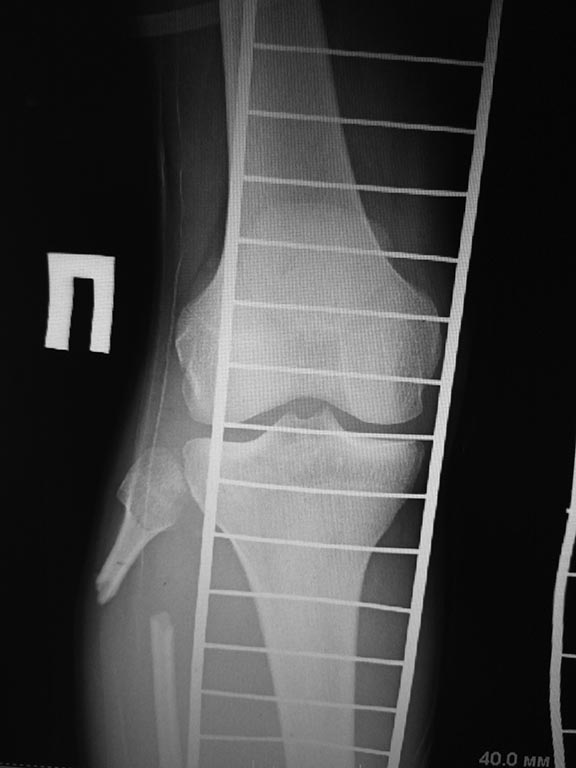

1 вариант, учитывая скомпроментированную суставную поверхность

б/берцовой кости, выполнить ретроградно  штифтом  артодез с фиксацией

перелома б/берцовой кости. Выполнить рассверливание и открыто не

вмешиваться.

2 вариант)  микрохирурги предлагают открыться на место перелома

б/берцовой кости, удалить нежизнеспособную кость и выполнить

трансплантацию м/берцовой кости с другой голени ,  на сосудистой ножке.